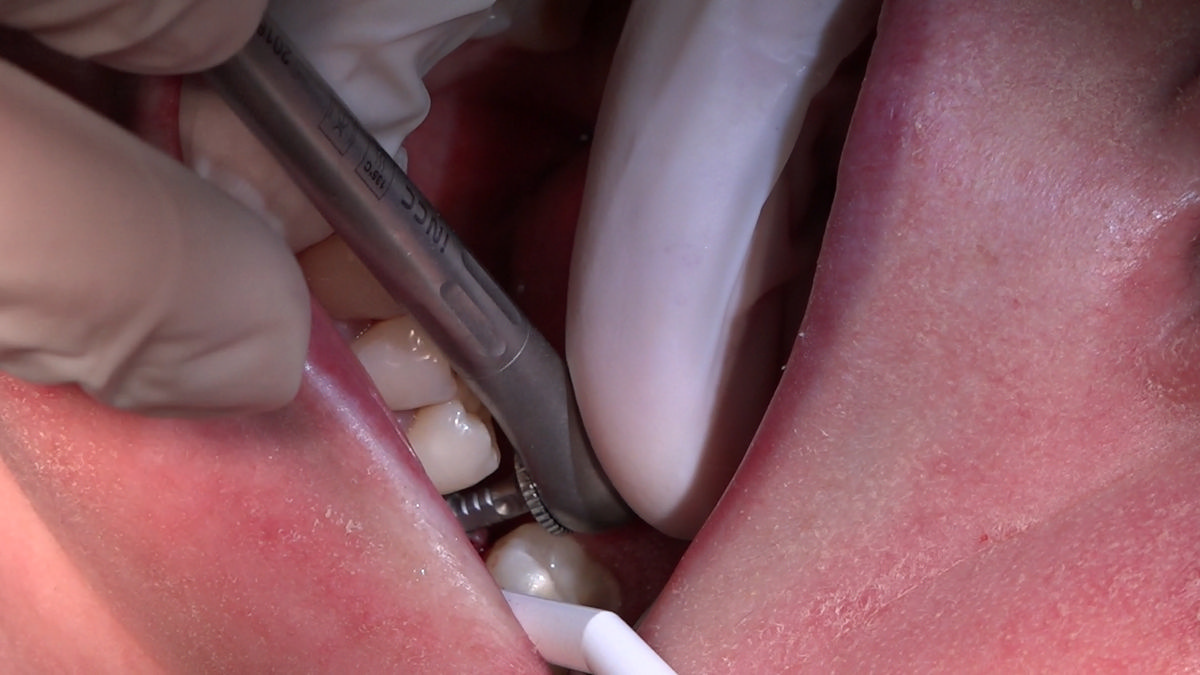

PRACTICULUM IMPLANTOLOGII - SEZON X - SESJA 4 - GRUPA B